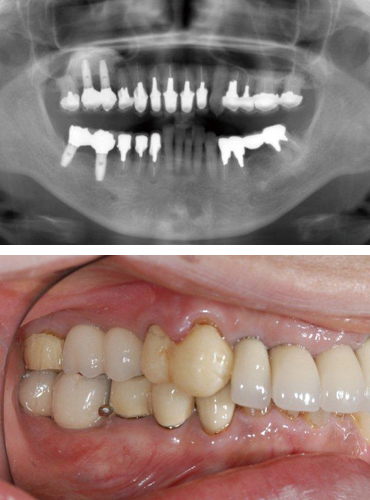

インプラント治療を行う前の検査として、一般的にはレントゲン撮影による術前診査が行われますが、レントゲン撮影によるレントゲン像は全顎的な診査を行うためにはとても有効ですが、インプラント治療の術前検査としては完璧なものではありません。

例えば、インプラント手術において危険領域となる神経管や血管の位置や骨幅、骨質などを正確に診査・診断するためにはCTによる精密検査は欠かすことはできません。

撮影したCTデータをもとにして、コンピューター上で3Dシミュレーションすることができるのも、デジタル診療の大きな利点であり、これにより理想的な治療計画が立てられます。

当院では、まず審査・診断を行い、CTによる精密検査、コンピューター3Dシミュレーションでのインプラント手術設計、サージカルガイドによるガイデッドサージェリーでのインプラント治療、治癒期間という流れになっております。

インプラント手術後